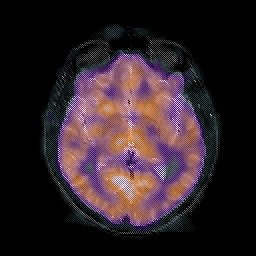

AIDS dementia: overlay -- Slice #8

[Home][Help][Clinical][Tour 1] Slice 8